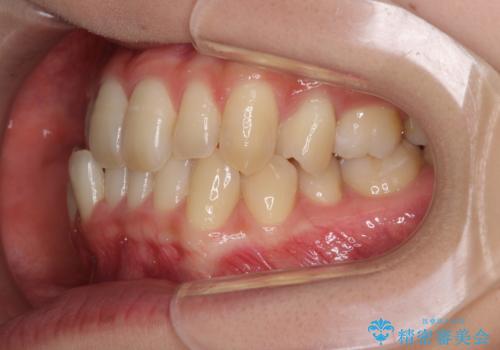

奥歯の反対咬合 上顎骨を拡大してインビザラインで矯正

- 奥歯の反対咬合を気にして来院された患者様です。

反対咬合は上顎骨の幅が下顎骨よりも小さいことが原因なので、拡大装置により骨幅を広げて上下関係を改善し、その後インビザラインにて歯並びを整えることとしました。

反対咬合が改善され、食いしばり癖もなくなり、顎関節の負担が軽減されました。

上顎骨を拡大したことで前歯に隙間ができ、1ヶ月ほど恥ずかしい時期がありましたが、しっかりとした咬み合わせに仕上がり、患者様には大変満足していただきました。